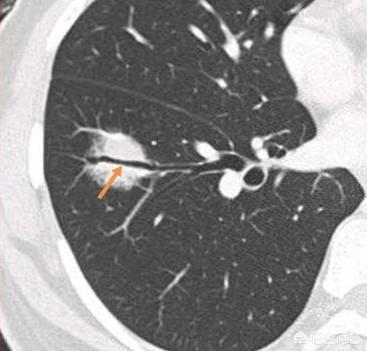

肺結節を見つけるための次のステップは、良性か悪性かを判断することである。良性の結節は、肺のリンパ節、形の悪い腫瘍、硬化性肺細胞腫など、間違いなく何でもないものである。残りの結節は良性または悪性の可能性があるもので、このような結節に対する治療の一般原則は経過観察を勧めることであり、結節の特異性(形態、大きさ、密度など)に応じて、見直しの時期は3ヵ月から1年である。結節の中には、炎症性結節のように経過観察中に吸収されて消失するものもあれば、肉芽腫のように変化しないものもあり、これは良い情報である。経過観察中に、結節の肥大、すりガラス結節の中の実成分や固形成分の増加、結節の緻密化、末梢血管が伸びているのが見えるなど、悪性の徴候があれば、積極的に対処すべきです。実際、人を見るように、正義の顔は、一般的に良い人、凶暴で悪質な悪人であり、いくつかの一時的な人の行動の観察を通じてのみ見ることができない、ルールは一般的に恐れていない場合は、悪い行動があることを発見した場合は、タイムリーに対処する必要があります。図1、左肺上部のすりガラス状の結節(オレンジ色の矢印)を発見し、2年以上経過観察したが変化なし。図2、右肺上部に2個の小さなすりガラス結節(オレンジ色の矢印)、2年後に消失した。図3、右肺上部のすりガラス状の小結節、3回目の経過観察で大きくなっているので、前向きに対処することを勧め、外科的病理検査でin situ癌、つまり前癌病変を発見すれば、肺癌の芽を摘むことができる。

結節といえば、まず肺の小結節の症例を見てみよう。 この患者は風邪で咳があり、胸部CT検査で右肺にすりガラス状の結節が見つかり、層厚1mmの右肺上葉のCT断面像で、大きさ6mm、その固形部分(矢印)は4mm以下の部分固形結節を認めた。境界は明瞭で、病歴から炎症性であると考えられ、炎症の再検討を勧められた。

3ヵ月後のフォローアップCT画像では、病変は完全に消失しており、良性の病因と一致した。

この症例は、肺の小さな結節がすべて悪性であるわけではなく、すべてが肺癌になるわけではないことを示している。